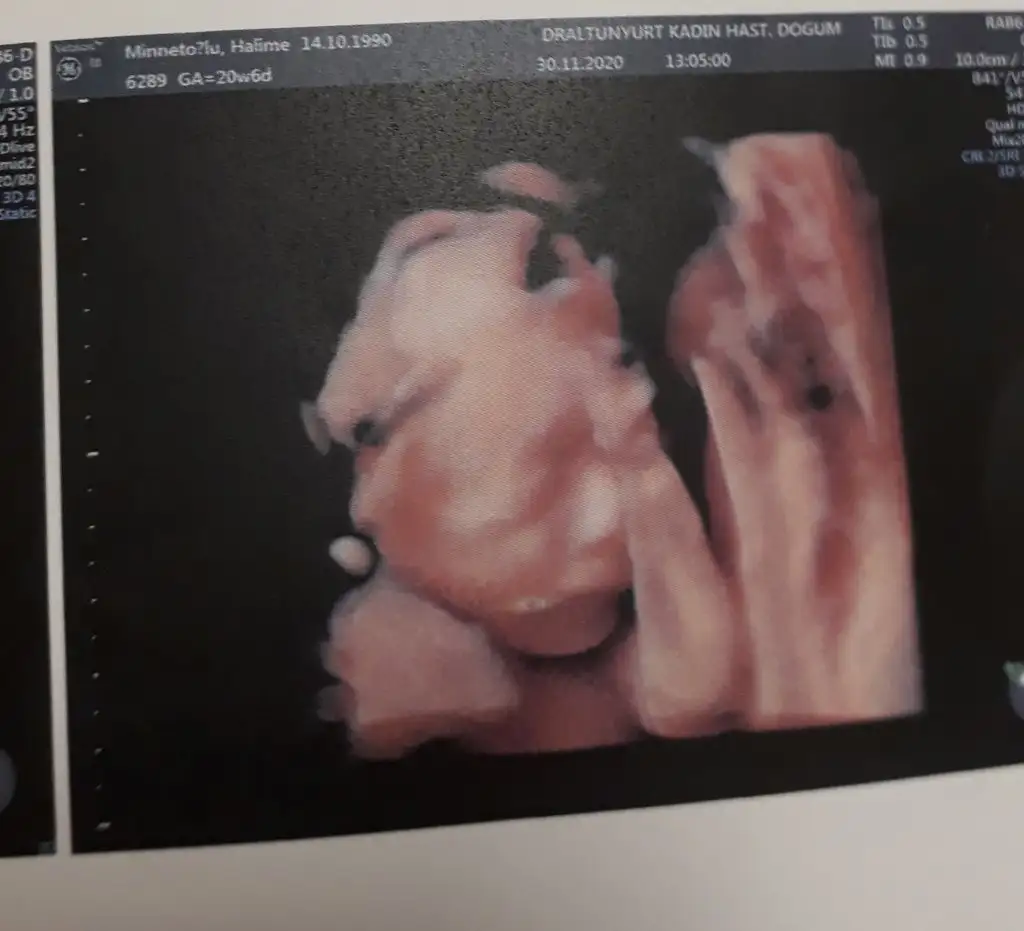

Maşallah canım bu bebişlerin elleri hep kafalarında benim oğluşumunda eli kafasındaydı son kontroldeOğluşum teyzeleri